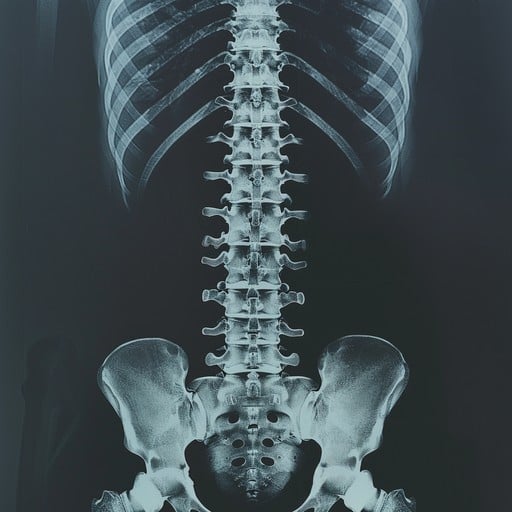

脊髄損傷による麻痺に新たな光:3Dプリンターと幹細胞で神経回路を再建

一度損傷すると完全な回復は難しいとされる脊髄。この大きな課題に対し、3Dプリンター、幹細胞生物学、そして研究室で培養した組織を組み合わせた画期的なプロセスによって、脊髄損傷からの回復を実証した研究が登場しました。

米国立脊髄損傷統計センターによると、米国では30万人以上が脊髄損傷に苦しんでいますが、損傷によるダメージやまひを完全に元に戻す方法は確立されていません。大きな課題は、神経細胞が死んでしまうこと、そして神経線維が損傷部位を越えて再生できないことにあります。今回の新しい研究は、この問題に正面から取り組むものです。